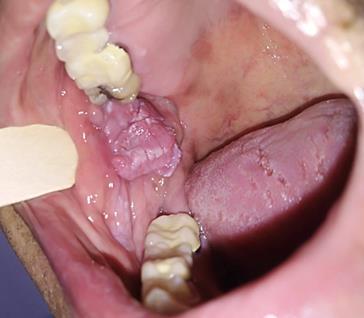

Presentación de caso clínico

Paciente masculino de 61 años de edad. Presenta lesión en la mucosa yugal derecha con forma de pápula de superficie rugosa adoptando una forma de coliflor de aproximadamente 2 cm, de consistencia fibrosa;de1añodeevolución.(Fig5).

Microscópicamente, las lesiones exhibenuna arquitectura exofíticay papilar con una base amplia. El epitelio puede ser moderadooacentuadamenteacantósicocon crestasreticularesbulbosas(Sato1997).En ocasiones, puede identificarse paraqueratosis con invaginaciones que rellenan las crestas entre las papilas (Eversole,2000).

5.

Condiloma acuminado, imagen clínica

Nota: Condiloma acuminado, imagen clínica (Foto cortesía de la Dra. Aurora Pérez Baché)

Setomabiopsiaescixional dondese observa epitelio escamoso estratificado con acantosis y escasa paraqueratosis, con prolongaciones epiteliales densas y elongadas, así como células coilociticas y crecimiento exofiticos (Fig 6). Después de entregar el diagnóstico de patología se recomendó seguimiento a largo plazo debido a que en algunas ocasiones puede habertransformaciónmaligna.